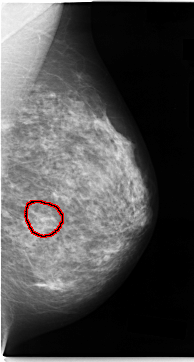

ics_version 1.0 filename C-0060-1 DATE_OF_STUDY 11 3 1993 PATIENT_AGE 47 FILM FILM_TYPE REGULAR DENSITY 3 DATE_DIGITIZED 23 10 1997 DIGITIZER LUMISYS LASER SEQUENCE LEFT_CC LINES 4704 PIXELS_PER_LINE 2624 BITS_PER_PIXEL 12 RESOLUTION 50 OVERLAY LEFT_MLO LINES 4704 PIXELS_PER_LINE 2512 BITS_PER_PIXEL 12 RESOLUTION 50 OVERLAY RIGHT_CC LINES 4704 PIXELS_PER_LINE 2696 BITS_PER_PIXEL 12 RESOLUTION 50 OVERLAY RIGHT_MLO LINES 4712 PIXELS_PER_LINE 2672 BITS_PER_PIXEL 12 RESOLUTION 50 OVERLAY |

FILE: C_0060_1.LEFT_CC.OVERLAY TOTAL_ABNORMALITIES 1 ABNORMALITY 1 LESION_TYPE CALCIFICATION TYPE AMORPHOUS DISTRIBUTION CLUSTERED ASSESSMENT 4 SUBTLETY 2 PATHOLOGY MALIGNANT TOTAL_OUTLINES 1 BOUNDARY |